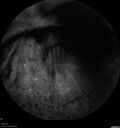

74 year old man with diabetes for about 40 years. No previous problems or treatments: EXTENDED HPI: Starting a little less then a week ago he woke up with something in the left eye. He saw a big blob in his vision. Since it started it is not getting better (also not getting any worse). The right eye is OK. This has not happened before. He is on ASA and Clopidogrel. VA OD: sc20/20+2 NscJ7-1 VA OS: sc20/63-2 NscJ2

Vitreous Hemorrhage with no evidence of PDR in the left eye371 views74 year old man with vision loss OS for about a week. The FA shows no PDR in the left eye but the right eye has very mild NVD. Diabetes for 40 years now on insulin.00000